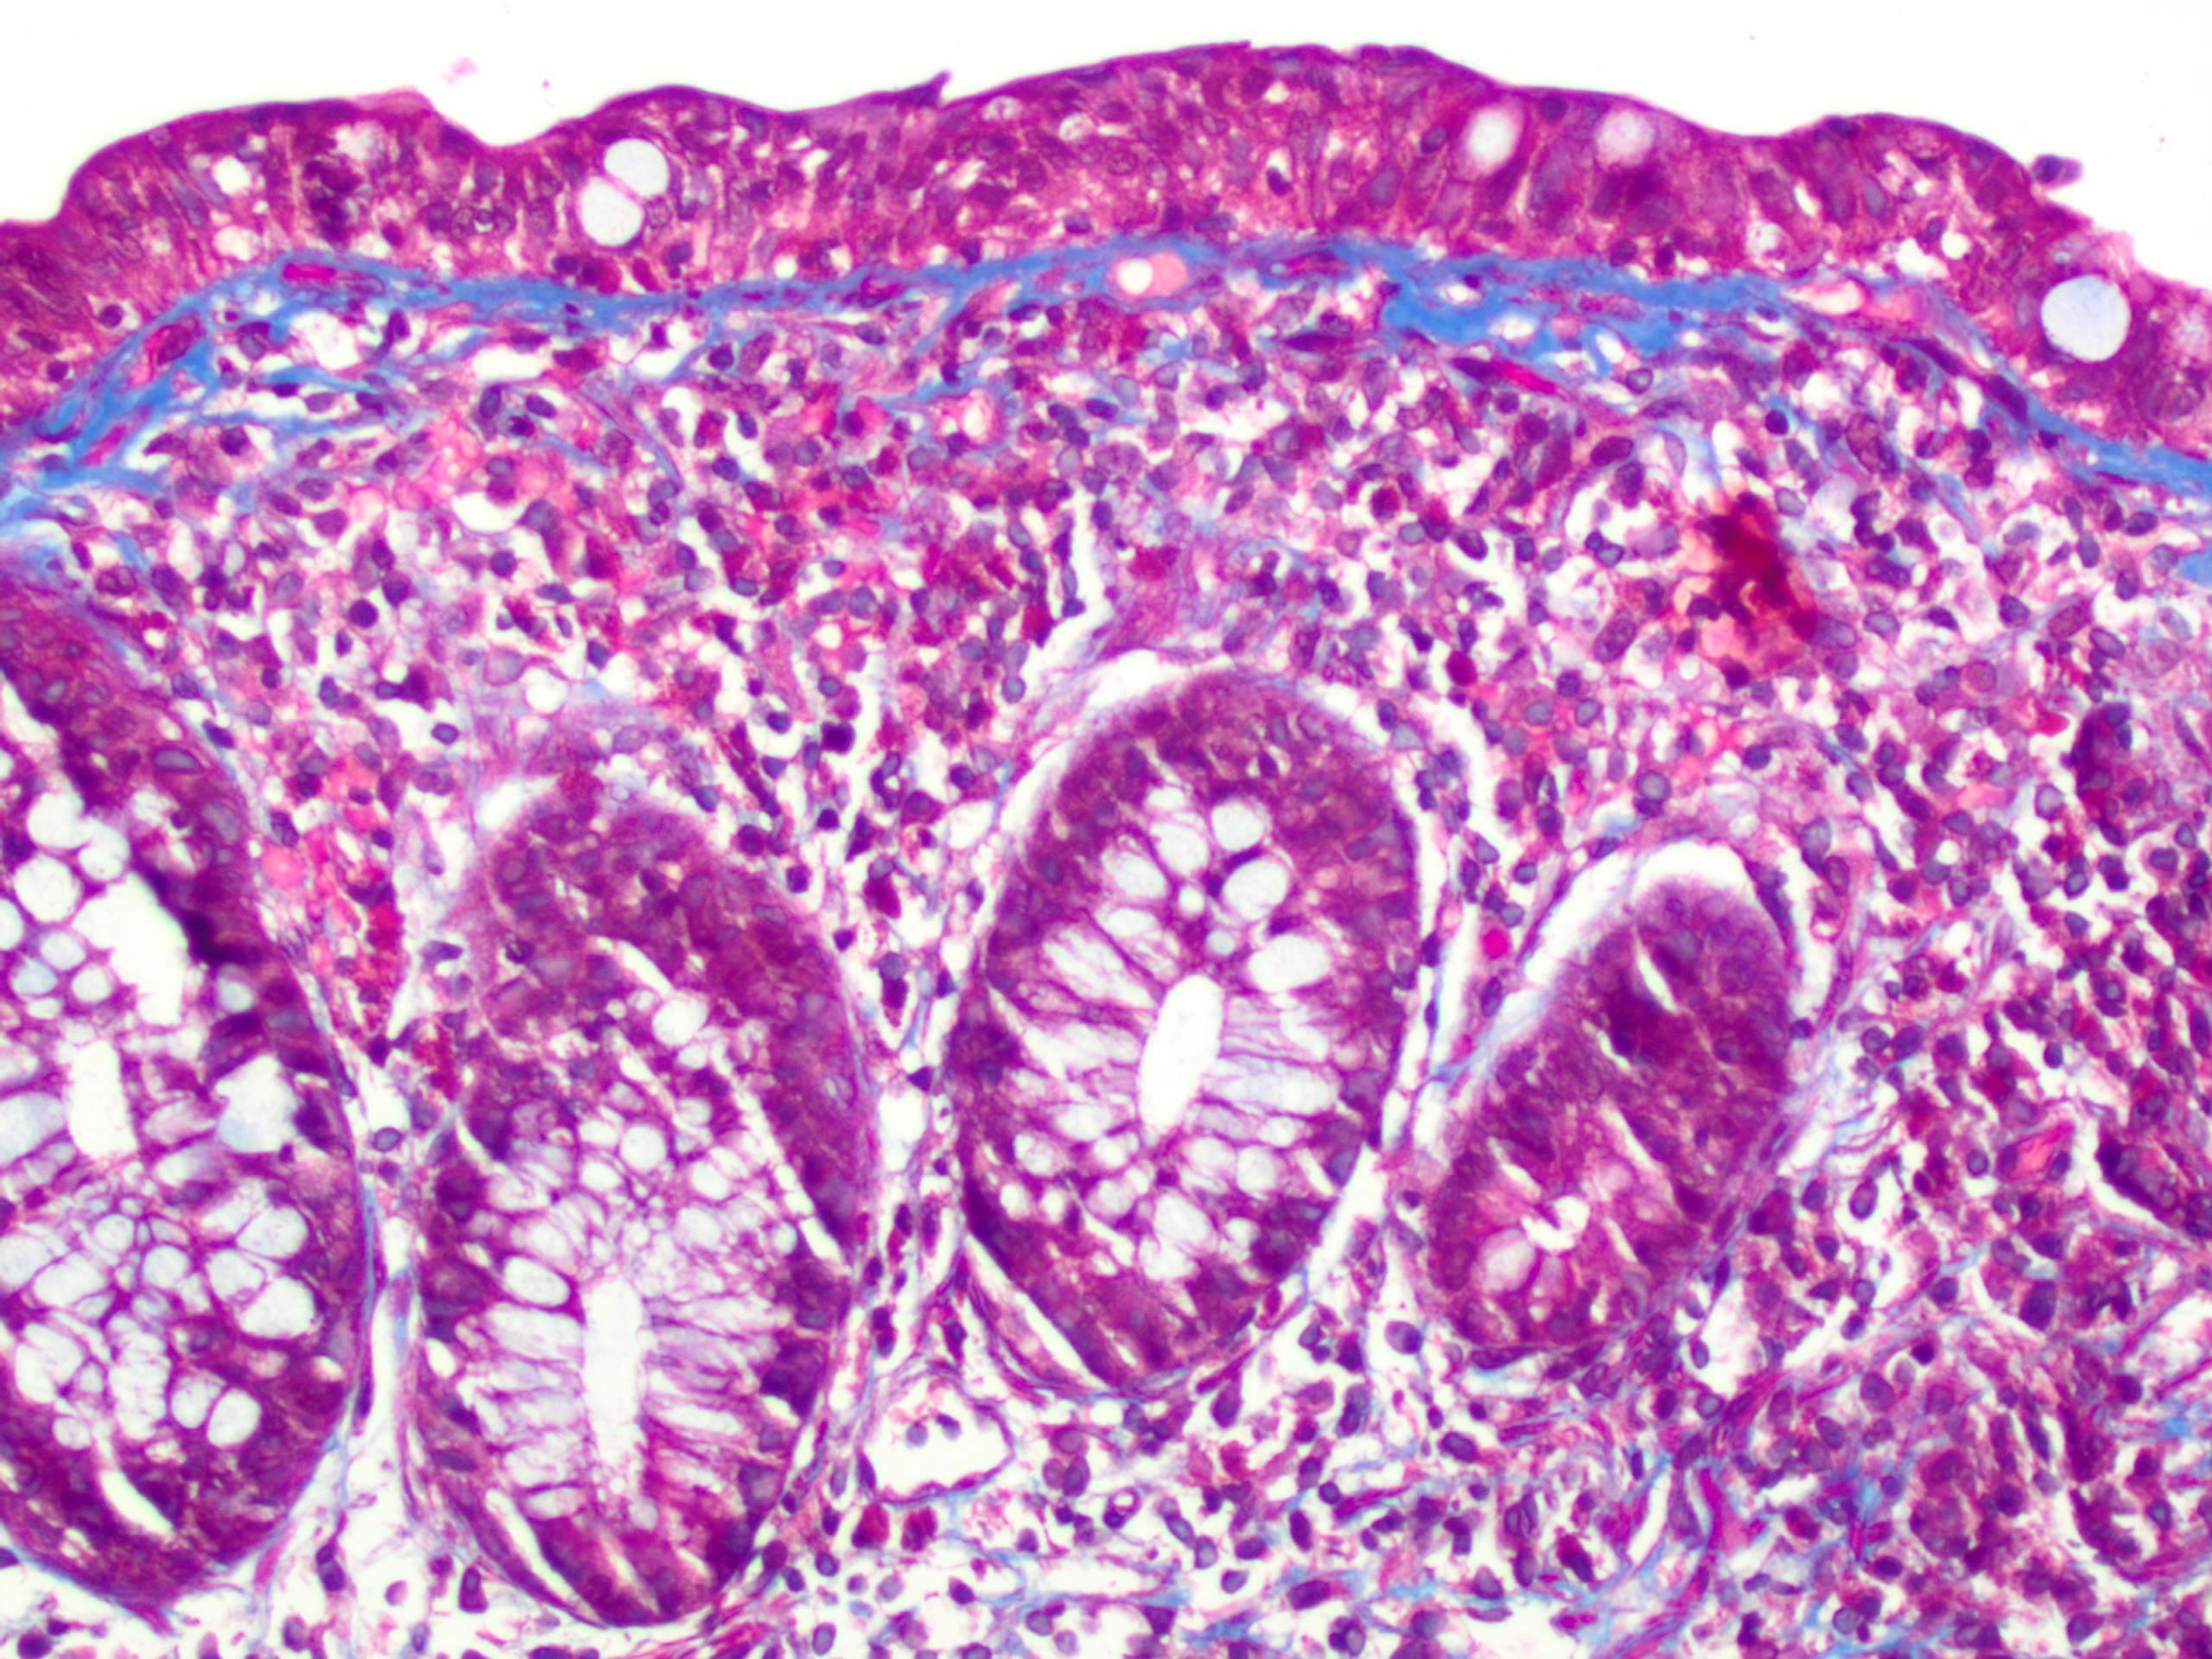

Microscopic (histologic) description

- Thickened subepithelial collagen band, usually with capillary, red blood cell and inflammatory cell entrapment (Histopathology 2015;66:613)

- Collagen band typically > 10 microns

- Occasional cases can have an irregular collagen band that is < 10 microns; some have labeled such cases as "incomplete collagenous colitis"

- Trichrome stain can be useful in equivocal cases

- Surface mucosal damage with loss of mucin, flattening and detachment

- Increased lamina propria inflammation composed of lymphocytes, plasma cells and eosinophils

- Neutrophilic inflammation can be seen but is typically not prominent

- Increased intraepithelial lymphocytes; may be mild (< 20 per 100 epithelial cells)

- Crypt architecture is preserved or minimally distorted

- Masson trichrome stain highlights the subepithelial collagen band